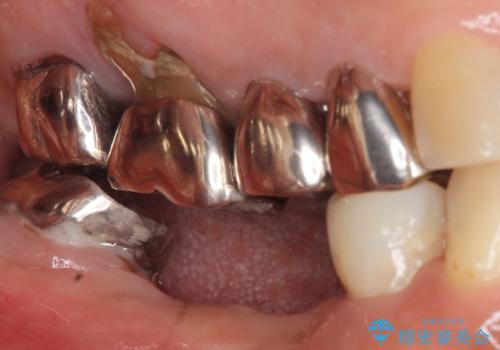

- 奥歯のインプラントをご希望され、来院された患者様です。

骨が薄いため、他院ではインプラントできないと言われたとの事でした。

精査したところ、右下4の根尖病変及び右下5の欠損を認め、右下6は残根となり保存不可能な状態でした。

保存不可能な歯を抜去後、インプラント治療と根管治療を行いました。